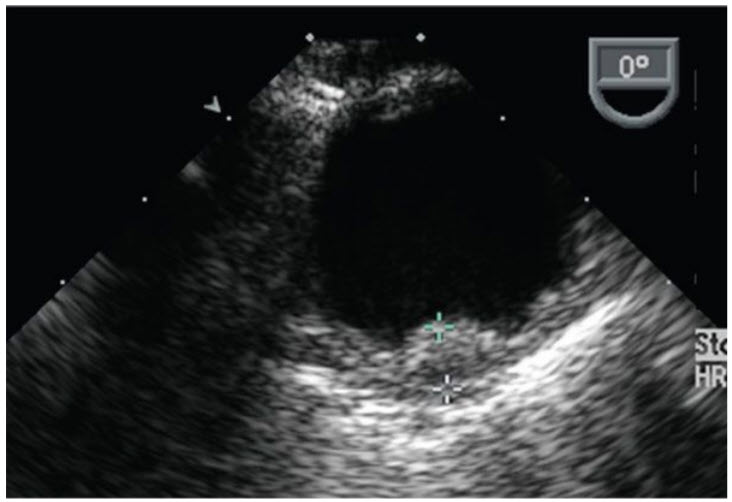

Which of the following medical regimens is most appropriate for a patient with a cardioembolic stroke and the following finding seen on TEE (figure below).

Statin and aspirin. The TEE shows a large protruding sessile atheroma in the distal descending aorta/distal aortic arch. Treatment for aortic atheroma remains controversial. Antiplatelet therapies such as aspirin and statins are the mainstay of treatment. Systemic anticoagulation with warfarin or warfarin alternatives is unproven due to limited data. However, several observational reports particularly for aortic arch atheroma demonstrate resolution or reduction of large mobile thrombus/atheroma and embolic events in patients on warfarin. Transesophageal echocardiogram with a short-axis view of the upper descending aorta. A large sessile protruding atheromatous plaque is seen (see figure in question)